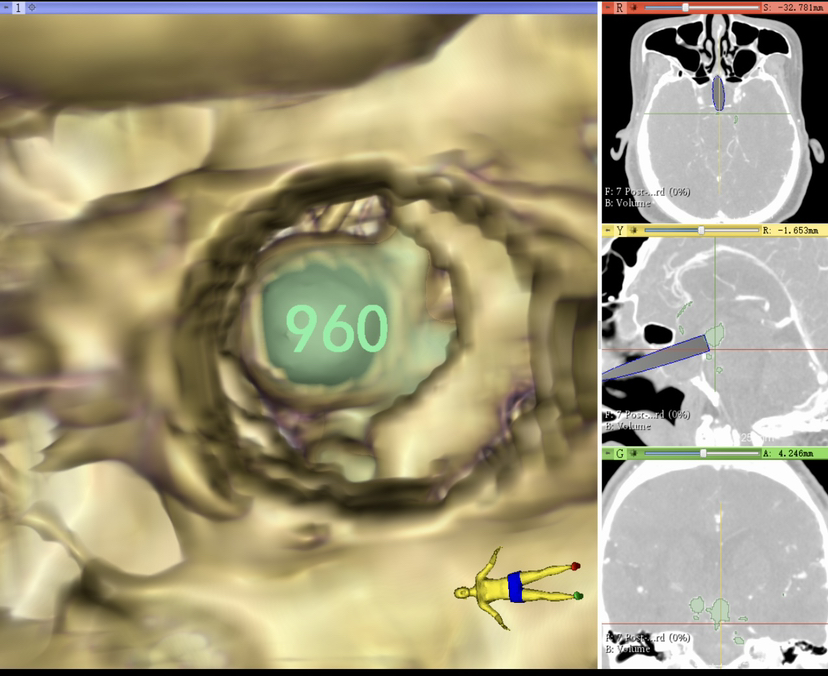

术前规划

制定虚拟内镜术前计划,显示鞍背阻挡动脉瘤颈部。

术中磨除鞍背骨质